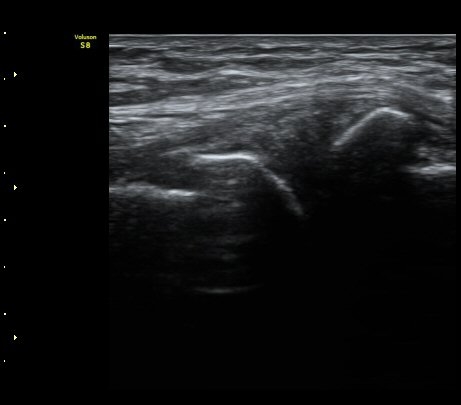

´ëÅð ³»Ãø, ¹«¸­ °üÀý¸é¿¡¼­ ¾à 10 cm ±ÙÀ§ºÎȾ´Ü¸é°Ë»ç¿¡¼­ ³»Ãø±¤±Ù°ú ºÀRHD±Ù(sartorius)

»çÀÌ¿¡¼­ º¹Àç½Å°æÀÌ °í¿¡ÄÚ Å¸¿øÇü ¾ç»óÀ¸·Î °í³ªÂûµÈ´Ù(»çÁø 2).